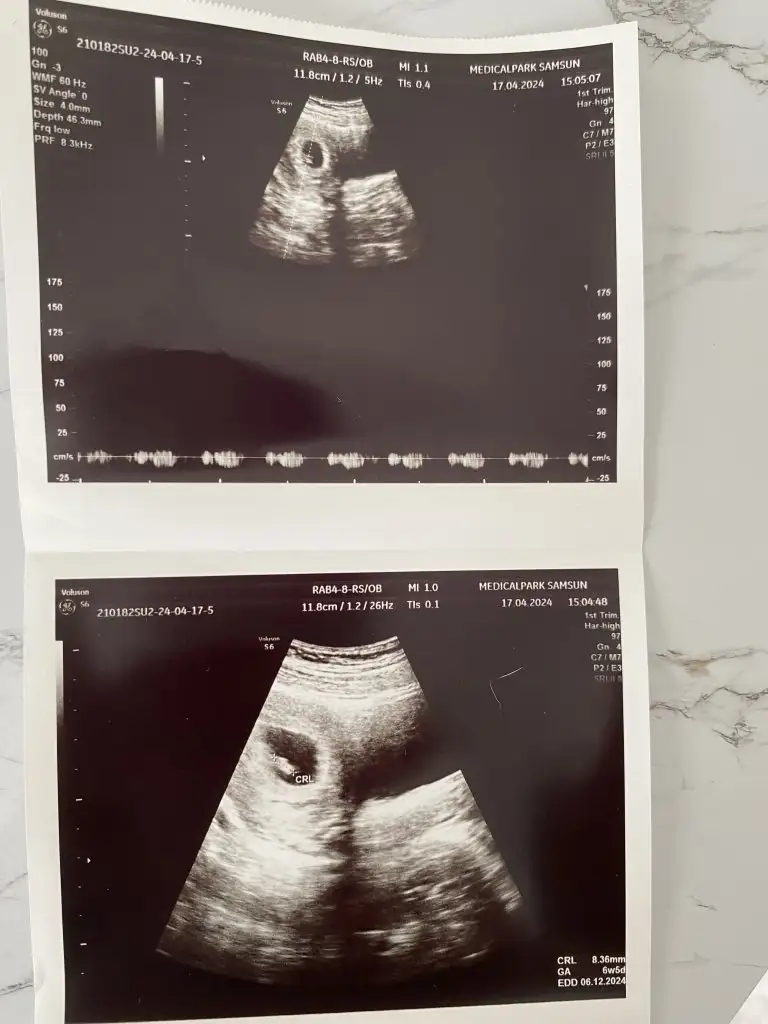

Bu dediğiniz vajinal olunca diye biliyorum normalde ramziye göre karından bakıldığında 6-7 haftaya kadar ultrason görüntülerinde sol ise erkek sağ ise kız sonra ki haftalarda geçerli değil çünkü bebiş hareket etmeye başladığı için yanlış sonuç verebilirkarından olunca ayna görüntüsü gibi düşünsağda olunca kız . solda olursa erkek. yani solda olması demek aslında sağda demek umarım yanlış söylememişimdir

Haaaa anladım yani embriyo solda olduğu için fotoğrafta sağda görünüyor ve solda olunca erkek oluyor genellemeye göre. Şimdi aklıma yattı. Zaten karından mı diye soruyorlardı ya onu da anlamıyordum ne alaka ne fark eder diyordumkarından olunca ayna görüntüsü gibi düşünsağda olunca kız . solda olursa erkek. yani solda olması demek aslında sağda demek umarım yanlış söylememişimdir

Canım şöyleymiş embriyo solda olduğunda karın ultrasonunda sağda görülürmüş. Yani bu soldaymış evet ve solda olduğunda kabule göre erkek oluyormuşHaa o da doğru benimki nerde ya ortada gibi

Na benim böyle, bebiş daha çok sağdaydı yani en azından karnımın sağından gördüü

seninkide sağda işte.Eki Görüntüle 3425141

Ama aynı durum için bana erkek dedin az önce :)seninkide sağda işte.yani normalde solda . buda kız demek oluyor. yani bence